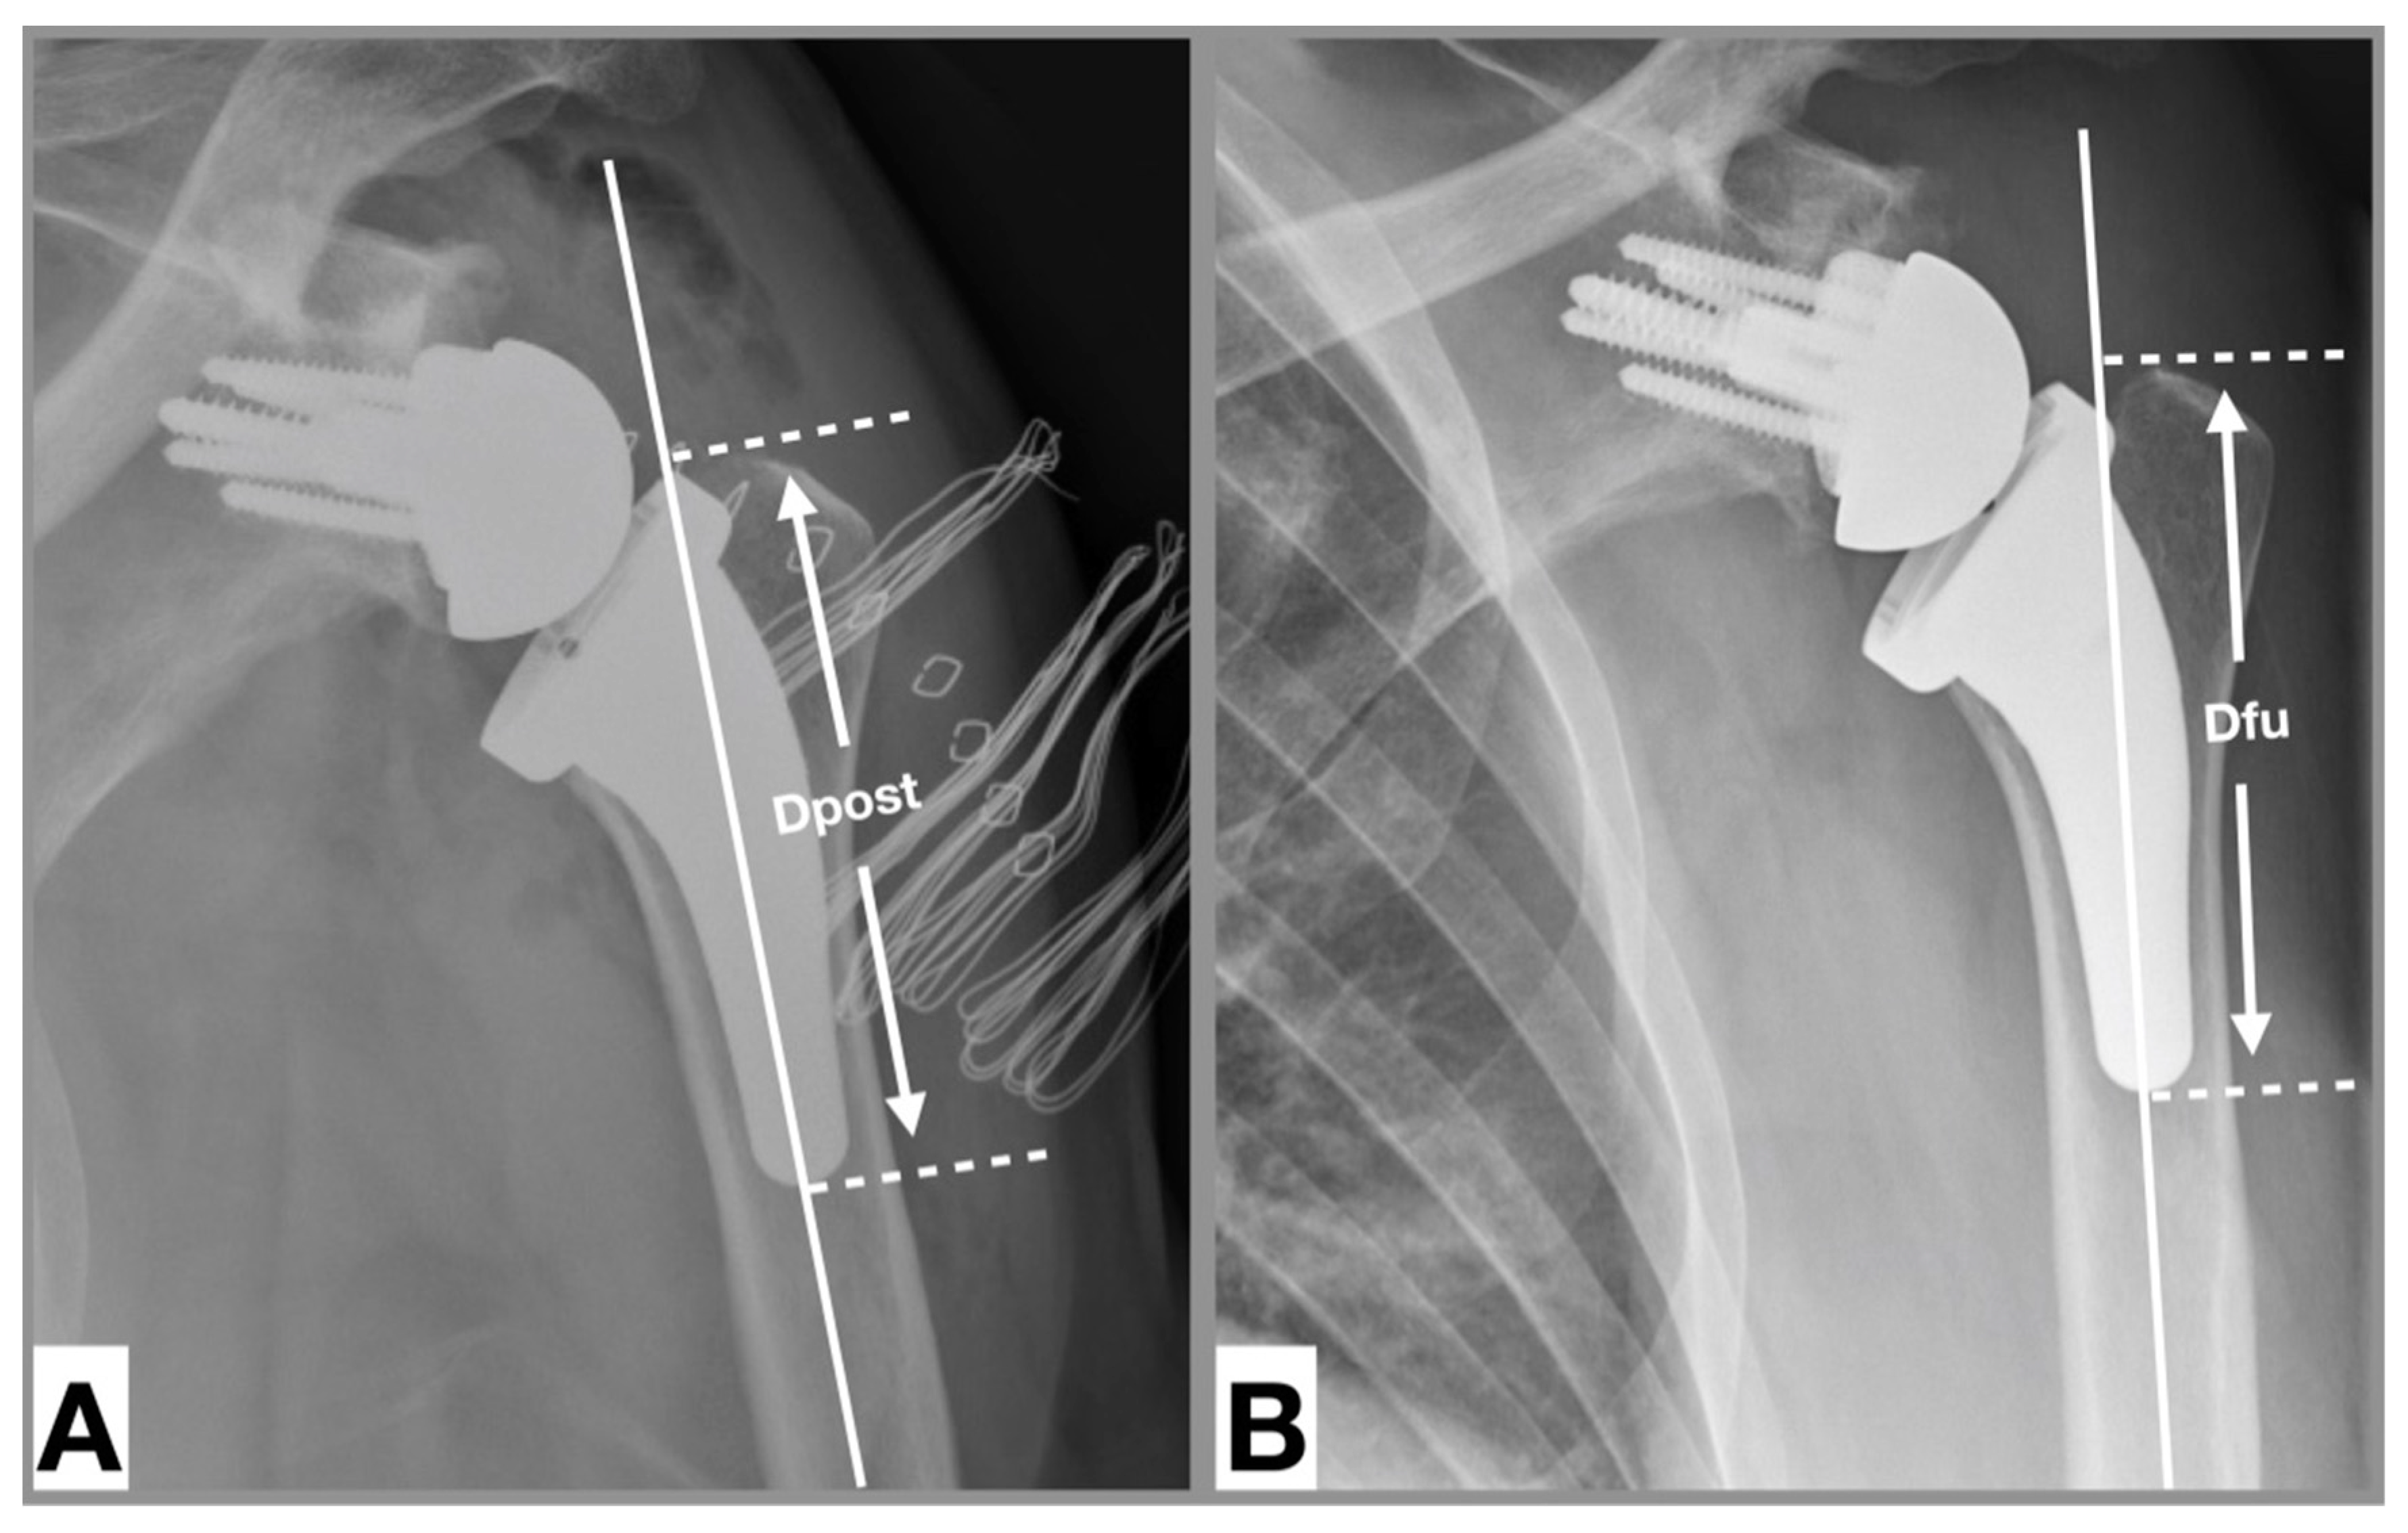

2.4. Radiographic Analysis

Two independent examiners performed radiographic measurements of 137 reverse USSPs on comparable anteroposterior radiographs immediately postoperatively and at final follow-up. Stem inclination (neutral/valgus/varus) was measured in degrees and the filling ratio of the humeral shaft was measured at the level of the metaphysis and diaphysis in millimeters according to the method introduced by Schnetzke et al. (Figure 2) [27]. If the angle of the stem relative to the humeral canal was ± 5 degrees, the inclination was considered as neutral. If the angle was >5 degrees the inclination was considered as valgus and if the angle was <5 degrees the inclination was considered as varus [31]. Cortical thickness was measured according to the method of Mather et al. [32]. Subsidence was determined by comparing the distance between the most cephalic aspect of the greater tuberosity with the distal border of the stem according to the method introduced by Bogle et al. (Figure 3) [33] and was empirically defined as an inferior migration of the shaft greater than 5 mm. Radiological results of patients who developed a postoperative complication were reported separately.

Figure 3. Measurement of subsidence [33]. Anteroposterior radiograph of a left shoulder. (A). Postoperative, (B). At 12 months follow-up. Shaft axis (solid white line), tip of tuberosity (white dotted line perpendicular to shaft axis), distal end of trabecular metal (white dotted line perpendicular to shaft axis). Subsidence: Distance between white dotted line at follow-up minus distance between white dotted line postoperative. Distances were calibrated based on the size of the glenosphere.